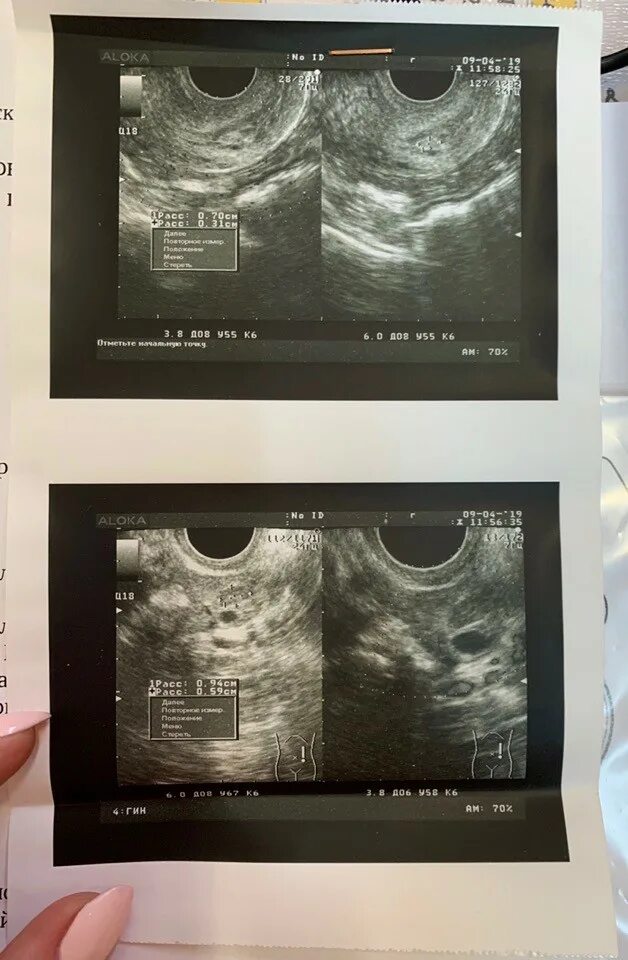

Узи не видит полип